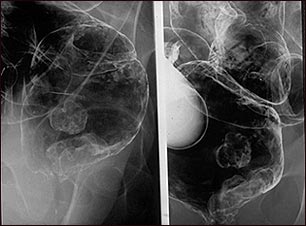

Rayos X de un cáncer rectal

Enema de bario en un paciente con cáncer de recto.